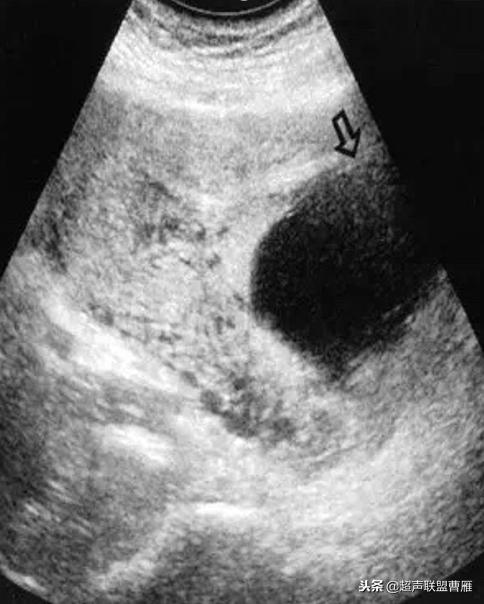

阴道超声检查诊断CSP

1.子宫空虚——宫内无妊娠囊

2.宫颈管空虚——宫颈管内无妊娠囊

3.子宫峡部前壁内见孕囊或不均质团块

4.孕囊与膀胱间的子宫肌层有缺陷,变的极薄或不连续

5.彩色多普勒血流显像显示孕囊或不均质团块周围有血流,流速增加